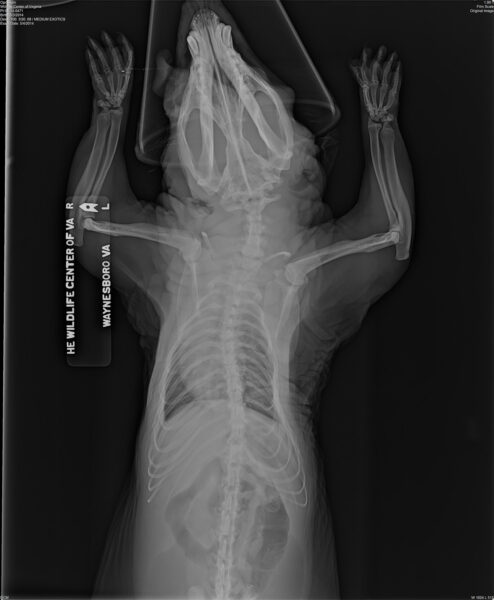

تُظهر هذه الصورة بالأشعة السينية لحيوان أبوسوم تم الاحتفاظ به في الأسر تشوهات في العظام - انحناء في الساقين والعمود الفقري - والتي تحدث غالبًا عندما يتم إطعام الحيوانات الأسيرة وجبات غذائية غير مناسبة من قبل أفراد غير مدربين. مجاملة من مركز الحياة البرية في فيرجينيا